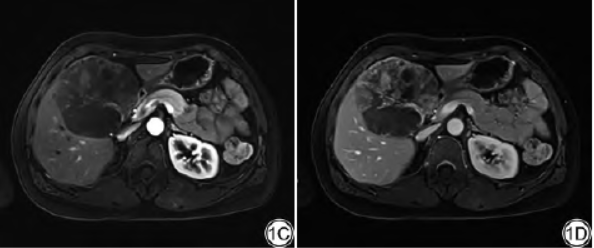

既往史:10年前因“畸胎瘤”行腹腔镜下卵巢切除术。上腹部MRI检查示:肝内见巨大类圆形混杂信号影,病灶大小约:8.7cm×7.7cm×11.1cm,T1呈低信号,T2压脂呈高信号,内见类圆形更高信号及分隔样低信号,增强扫描动脉期可见斑片样、结节样强化,门脉期、延迟期强化范围逐渐增大,强化信号不均匀(图1A~1E)。影像诊断:考虑血管源性肿瘤可能性大。

图1女,50岁,肝脏硬化性脂肪肉瘤。1A:T1WI病灶呈低信号;1B:T2WI压脂病灶呈高信号,内见分隔样低信号;1C:增强扫描动脉期可见斑片样、结节样强化;1D:门脉期强化范围增大;E:延迟期强化范围进一步增大,强化信号不均匀。1F:病理图,可见致密的胶原纤维化区域,梭形细胞有一定的异形性,核深染,不规则(HE×100)。